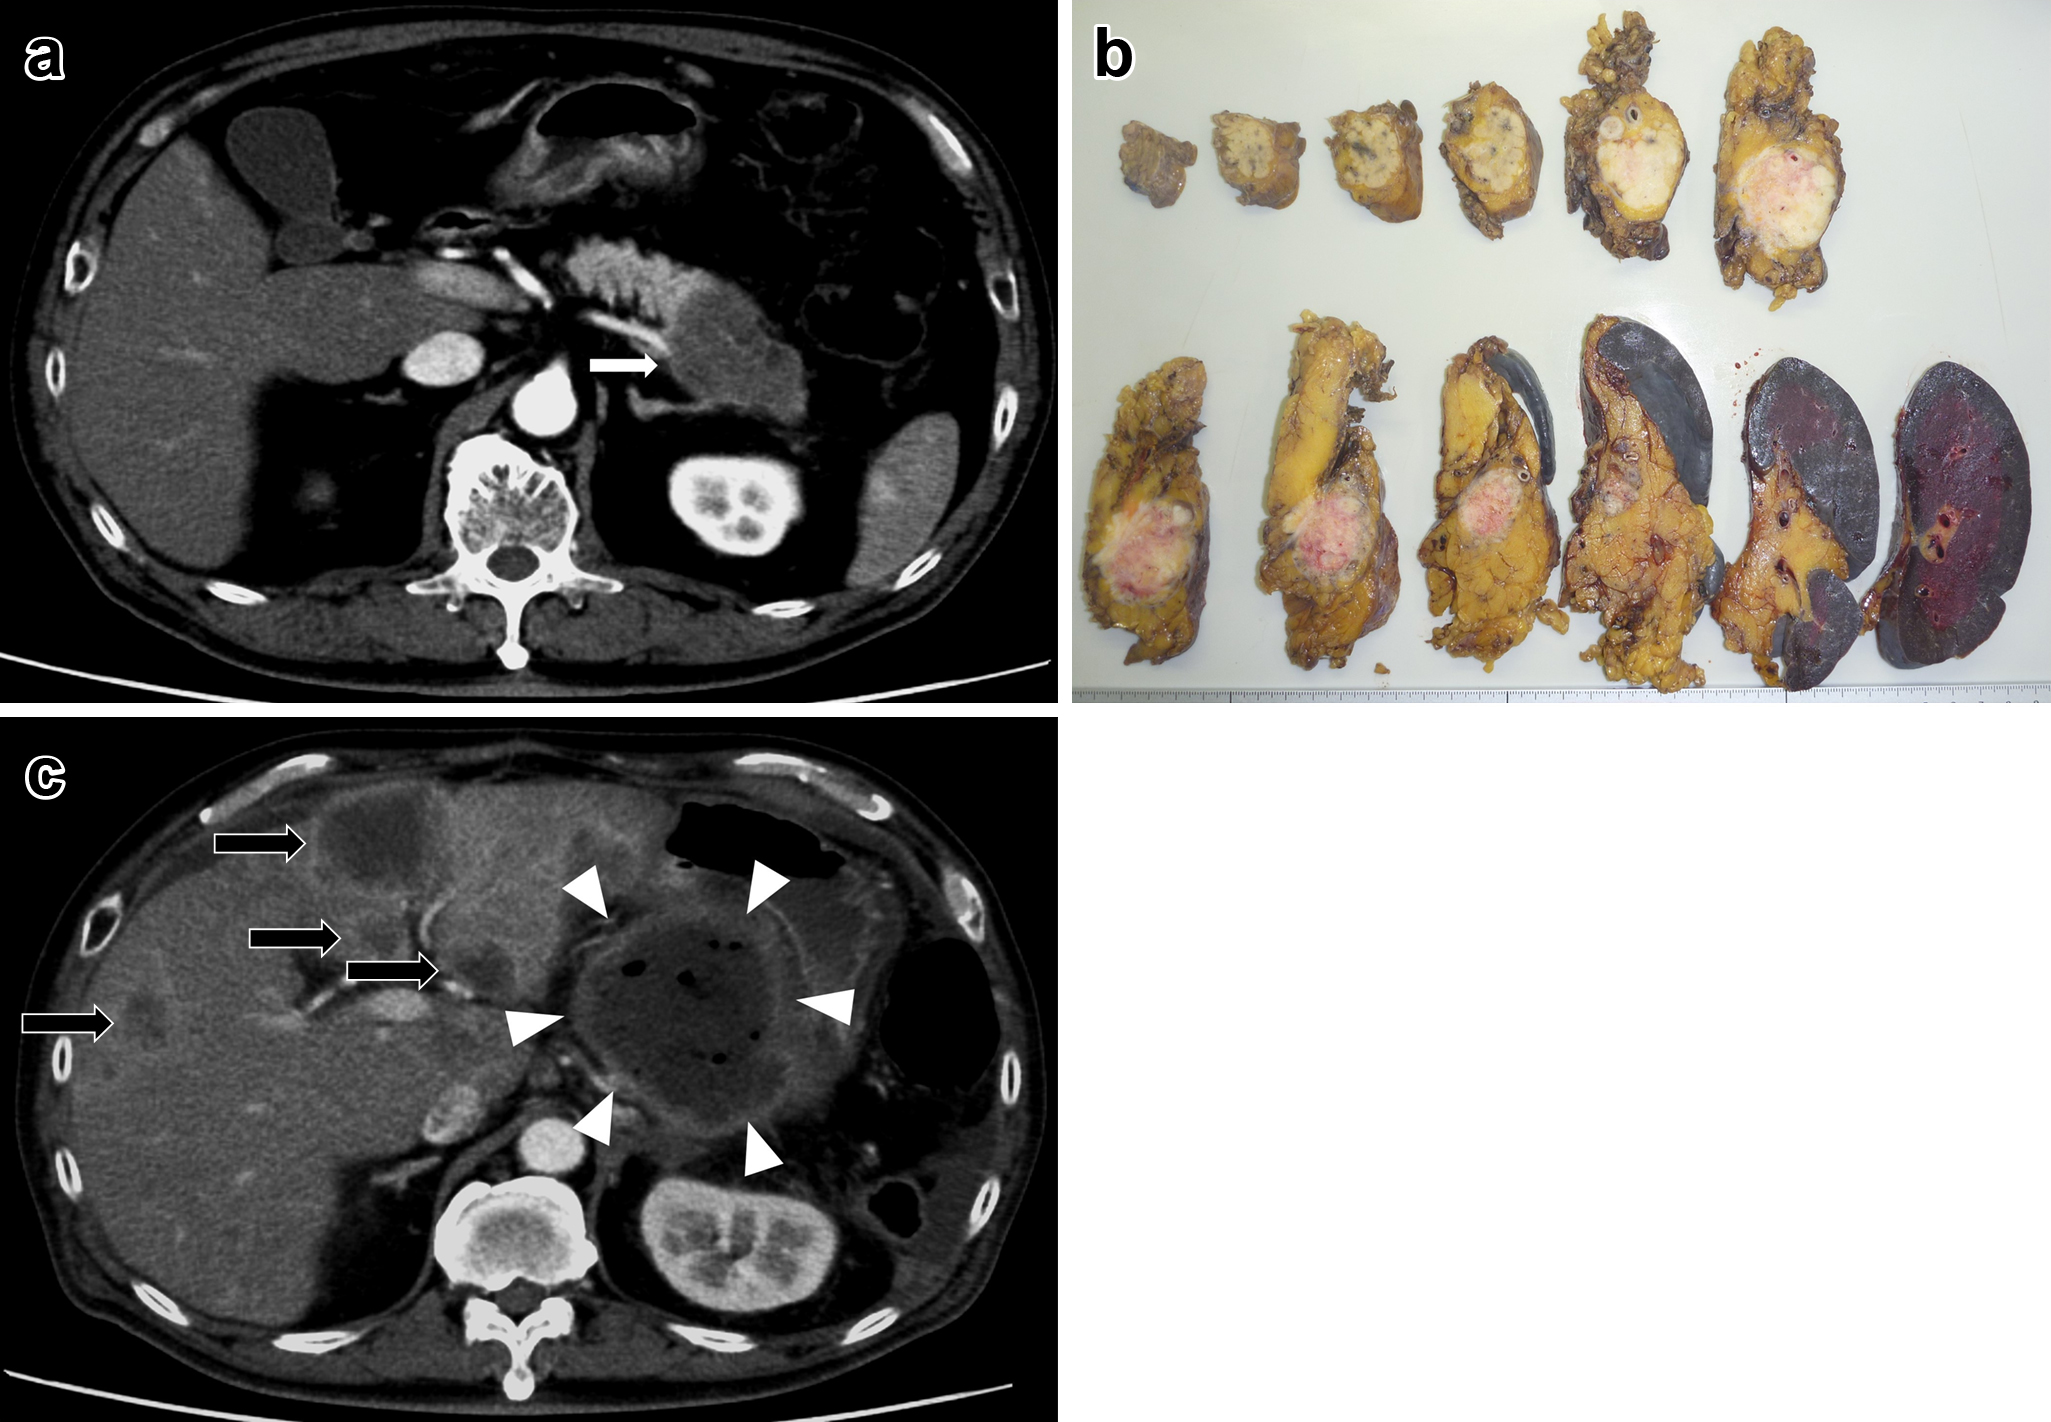

腹部造影CT所見:膵頭部に38×30 mmの乏血性腫瘤を認めた.上腸間膜静脈への浸潤が疑われた.肝臓に早期層で増強効果のある低吸収域を数か所認めた(Fig. 2a).

a: Abdominal CT scan showed a low density mass 38 mm×30 mm in the head of the pancreas (white arrow). b: The tumor was solid, and it was 40 mm in diameter. c: There were multiple liver metastases (black arrows).

切除標本所見:膵頭部に40 mmの白色充実性腫瘤を認めた(Fig. 2b).

最終診断:膵癌取扱い規約第7版に準じて,膵腺扁平上皮癌(Ph,TS3,nodular;pT3,int,INFb,ly2,v3,ne2,mpd1,pCH1,pDU0,pS1,pRP1,pPV0,pA0,pPL0,pOO0;pPCM1,pBCM0,pDPM0;pN1b Stage IIB)

経過:膵液瘻(ISGPF grade B)を合併したが,術後35日目に退院した.術後47日目に多発肝転移を認め(Fig. 2c),S-1内服を開始したが,徐々に全身状態が悪化し,術後84日目に死亡した.

腹部造影CT所見:膵尾部に59×33 mmの乏血性腫瘤を認めた.明らかな遠隔転移や腫大リンパ節は認めなかった(Fig. 3a).

a: Abdominal CT scan showed a low density mass 59 mm×33 mm in the tail of the pancreas. b: The tumor was solid, and it was 40 mm in diameter. c: There were multiple liver metastases (black arrows) and local recurrence (white triangles).

切除標本所見:膵体部から膵尾部にかけて40 mmの白色充実性腫瘤を認めた(Fig. 3b).

最終診断:膵癌取扱い規約第7版に準じて,膵腺扁平上皮癌(Pbt,TS4,infiltrative;pT3,sci,INFc,ly1,v1,ne1,mpd0,pCH0,pDUX,pS1,pRP1,pPVX,pA1(Asp),pPL1,pOO0;pPCM0,pBCMX,pDPM0;pN1a,M1(HEP)Stage IV)

肝結節からは腺癌成分と扁平上皮癌成分の混在を認めた.

経過:経過良好で,術後26日目からnab-paclitaxel+GEMを開始した.術後99日目に膵断端局所再発,多発肝転移を認め(Fig. 3c),cisplatin+GEMに変更したが,治療効果はprogressive diseaseであり,best supportive careの方針となって,術後307日目に死亡した.